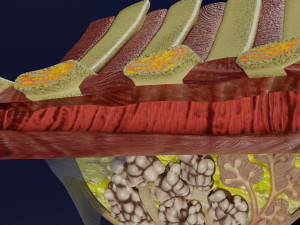

This is a 1:1 scaled model of right breast cut opened in sagittal plane to reveal its internal antomy and histology (schematic). The deeper parts and fascial layers are also depicted to give a very detailed approach to the model. The full layers starting from skin, nipple areola, till intercodtal muscles and ribs are also depicted.

breast mammary gland female chest wall anatomy human medical science reproductive genitalia muscle fascia milk nipple areola subcutaneous fatДо даного товару немає коментарів.